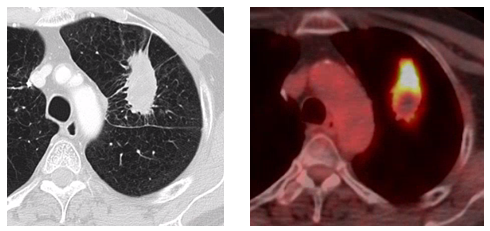

Figure B: SBRT treatment plan.

Upon evaluation Radiation Oncology agreed SBRT without biopsy was a valid treatment alternative to surgery with a preceding biopsy.9 Repeat CT and PET scans showed the lesion was expanding and demonstrated increasing PET positivity with a maximum SUV of 4.4 making malignancy very likely, and per NCCN guidelines should be resected without biopsy due to it’s baseline size and interval enlargement. This approach lacked a tissue confirmation of malignancy but the positive and increasing metabolic activity on PET scan, which are used to aid in the diagnosis of moderate risk lesions in the NCCN algorithm, did provide additional confidence in the diagnosis and course of action. The lesion, assumed to be a stage IA non-small cell lung cancer, was treated with SBRT to 48Gy in four fractions every otherday using 10 static IMRT fields with 6 MV photons based on 4D CT for treatment planning. The patient tolerated the procedure well and was scheduled for routine three monthly follow up visits with imaging.